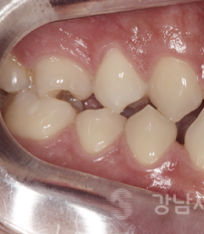

선수술교정 전/후

하지만 양악후 교정은 수술 직후

위 아래 치아의 교합이 불안정한

상태에서 교정을 진행해야 하기에

경력 있는 치과 의사들도 어려워 하는

까다로운 진료 방법이라고 했는데요.